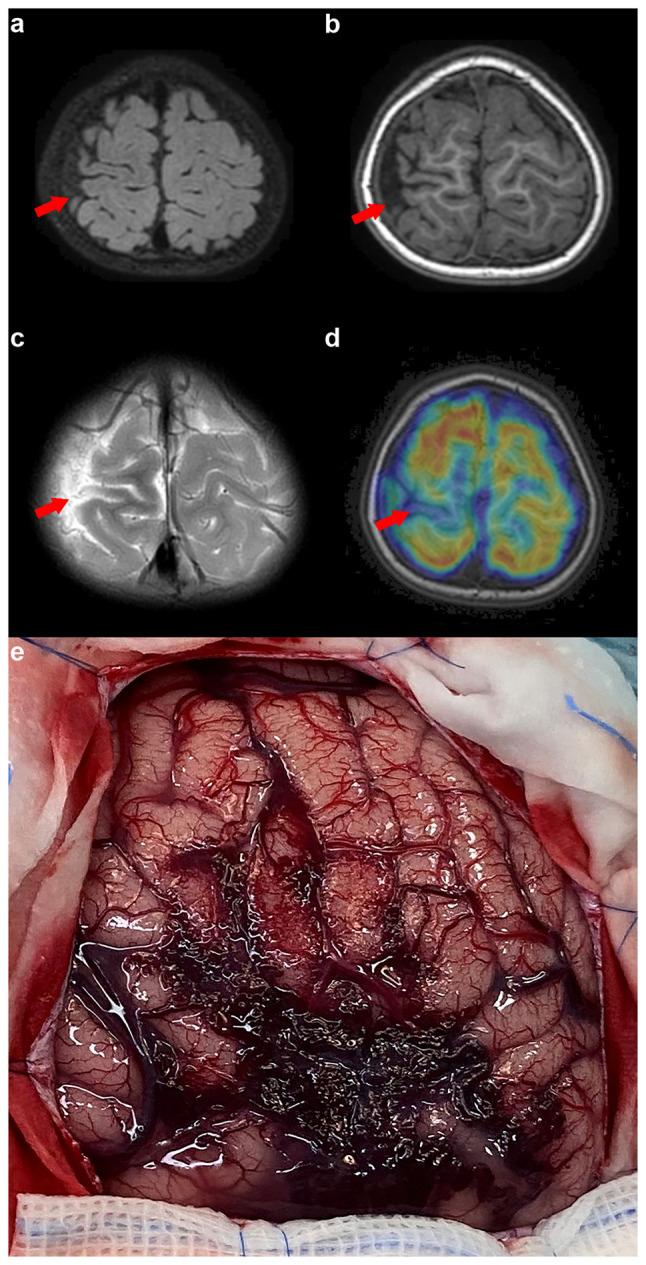

Sturge-Weber syndrome (SWS) type III, a rare neurocutaneous disorder, presents diagnostic challenges due to its variable clinical manifestations. The present study focuses on enhancing the understanding of this syndrome by conducting a detailed analysis of two pediatric cases and providing a comprehensive review of the existing literature. The cases, managed at the Children's Hospital Affiliated to Shandong University (Jinan, China), highlight the diverse clinical presentations and successful management strategies for SWS type III. In the first case, a 4-year-old male patient exhibited paroxysmal hemiplegia, epileptic seizures and cerebral angiographic findings indicative of left pia mater and venous malformation. The second case involved a 2.5-year-old male patient presenting with recurrent seizures and angiographic findings on the right side. Both cases underscore the importance of considering epileptic seizures, acquired and transient hemiplegia and cognitive impairments in the diagnosis of SWS type III. The present study provides insights into the effective use of both pharmacological and surgical interventions, drawing from the positive outcomes observed in these cases. The findings emphasize the need for heightened awareness and a meticulous approach in diagnosing and treating SWS type III, contributing to the better management and prognosis of this condition.

III型斯特奇-韦伯综合征(SWS)是一种罕见的神经皮肤疾病,因其临床表现多样而带来诊断挑战。本研究通过对两例儿科病例进行详细分析并对现有文献进行全面综述,着重加深对该综合征的理解。这两例病例在山东大学附属儿童医院(中国济南)接受治疗,突出了III型SWS的多样临床表现及成功的治疗策略。在第一例病例中,一名4岁男性患者表现为阵发性偏瘫、癫痫发作以及脑部血管造影结果显示左侧软脑膜和静脉畸形。第二例病例涉及一名2.5岁男性患者,表现为反复癫痫发作且右侧有血管造影结果。两例病例均强调了在III型SWS诊断中考虑癫痫发作、后天性和短暂性偏瘫以及认知障碍的重要性。本研究从这些病例中观察到的积极结果出发,深入探讨了药物和手术干预的有效应用。研究结果强调了在诊断和治疗III型SWS时提高认识和采取细致方法的必要性,有助于改善该疾病的管理和预后。